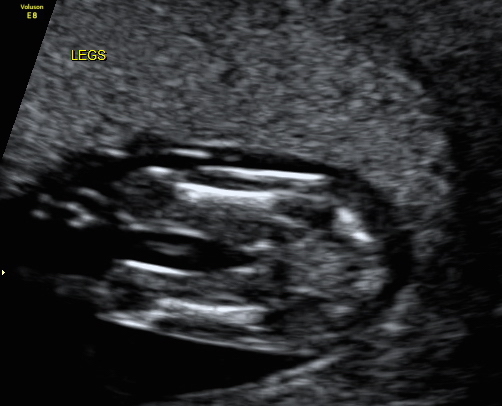

Hi, we have decided not to find out gender but i wanted to know what you ladies thought for a bit of fun while we wait! I'm not too sure if i can even see a nub in the profile but I thought someone here might be able too, also added the potty shot too, again i have no idea if you can see anything! Attachment 33072Attachment 33073